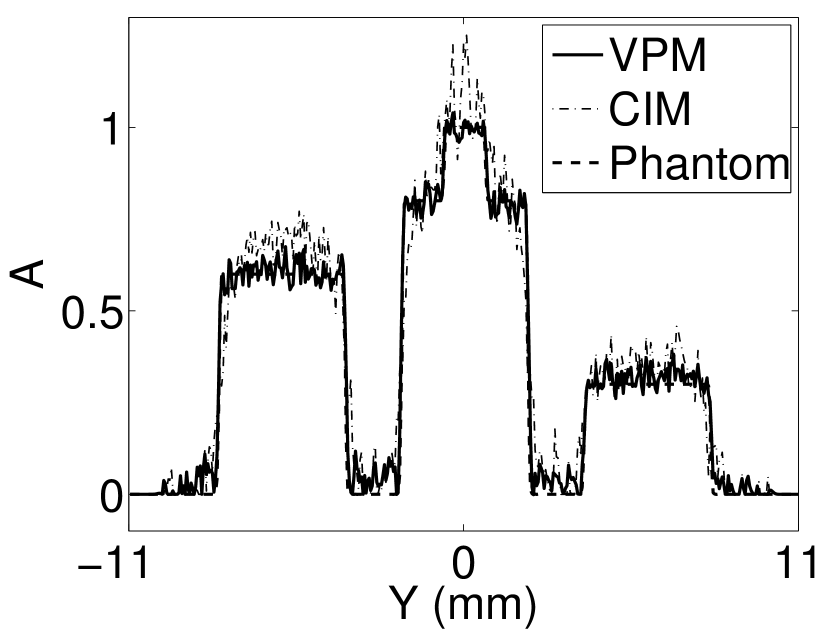

Figure 2(a) shows the image reconstructed by use of the conventional iterative method that utilized a system matrix based on EIR-2. Different values of the regularization parameter from the interval were considered. The reconstructed image with the value of that minimized the RMSE was chosen to represent the best performance of the conventional iterative method. Figure 2(a) and the profile in Figure 2(c) demonstrate that the use of an inaccurate EIR can result in strong artifacts and distortions in images reconstructed by use of the conventional methods.

When the VP algorithm was applied, different values of the regularization parameter from the interval and from the interval were considered. The image that minimized the RMSE was chosen and displayed in Figure 2(b). As revealed by this image and the profiles in 2(c), the VP algorithm yielded an image with fewer artifacts and distortions, and image fidelity was improved as reflected by the reduced RMSE.

The results shown in Figure 4 suggest that the reconstructed estimates of the EIR become more accurate when the bandwidth of the is increased (Figure 4(g) and 4(h)). On the other hand, the reconstructed estimates of become more accurate when the bandwidth of the EIR is increased (Figure 4(a) and 4(b)). For a given EIR, the reconstructed estimates of that contain sharp features contain more oscillations than the estimates corresponding to the smoothed versions of . This is because more high frequency information is lost during the convolution.

Figure 7(a) reveals that use of the inaccurate EIR in the conventional iterative method created strong artifacts and distortions. Figures 7(b) confirms that the artifacts and distortions were significantly mitigated when the VP method was employed. Image profiles for both cases are shown in Figures 7(c). The overall accuracy of the recovered EIR, shown in Figure 7(d) and 7(e), was improved, but it contained spurious oscillations.

Figures 12 and 13 show that the width of the needle in the reconstructed image increases as the regularization parameter increases for both the conventional iterative method and the VP algorithm. The images reconstructed by use of the VP algorithm appear to have a reduced noise level compared to the images reconstructed by the backprojection and conventional iterative methods, regardless of the choice of the regularization parameter values. The profile plots corresponding to these three methods are shown in Figure 14. Since the image of the coefficient vector and the EIR are recoverable only up to a multiplicative constant, every profile was normalized for comparison. These plots demonstrate that the image reconstructed by use of the VP algorithm possessed a more uniform background than those obtained by the backprojection and the conventional iterative methods.

The images and EIRs reconstructed by use of the VP algorithm that was based on the 2D imaging model that neglected the SIR are shown in Figures 15 and 16. The latter figure contains results corresponding to different values for the regularization parameter . From Fig. 15, it can be observed that use of the conventional iterative method that utilized the measured EIR resulted in distortions and loss of details in the reconstructed images. Use of the VP algorithm improved the contrast and the details in the reconstructed images (Fig. 15(c) and 16(a)). Furthermore, the images reconstructed by use of the VP algorithm had a more uniform background.

Similar to the case described above where the transducer SIR was neglected, these results reveal that use of the VP algorithm can produce images with a cleaner background and enhanced spatial resolution than yielded by use of a conventional iterative algorithm that employed the measured EIR. For example, detailed information regarding the vessels near the organ’s periphery was better preserved by the VP algorithm than by the conventional iterative algorithm. These images corroborate our assertion that the VP algorithm can significantly reduce the artifacts and distortions in the reconstructed image. It is also worth pointing out that, unlike the numerical phantom studies, the artifacts and distortions in the images may be caused not only by the inaccurate EIR but also by other factors, such as neglecting acoustic heterogeneities and the variation of the EIRs among the elements of the transducer array. In such cases, the EIR estimated by the VP algorithm represents an effective system impulse response that minimizes the inconsistency between the measured data and the imaging model.